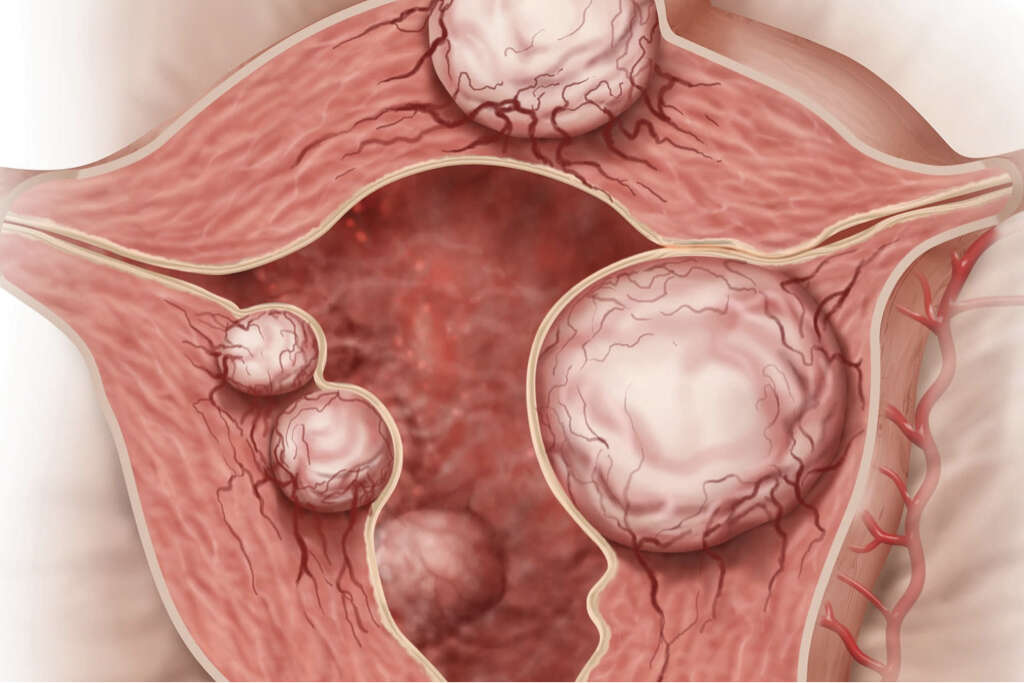

Uterus Ultrasound Normal Vs Intramural Fibroid Images Uterine

Fibroids What Are Fibroids

Fibroids What Are Fibroids